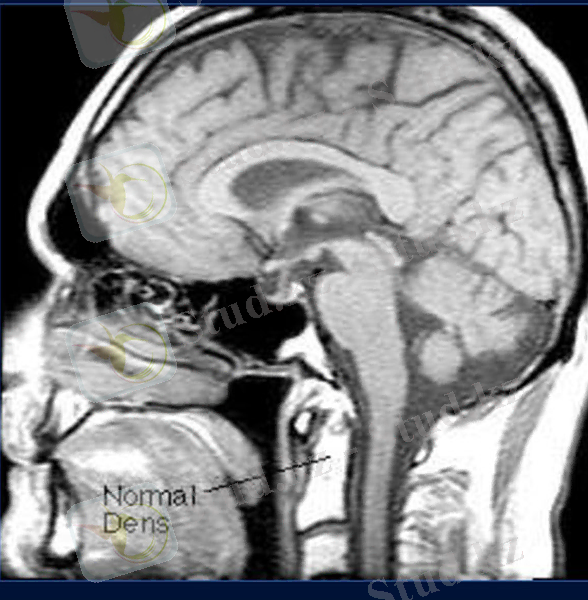

Магнитты - резонансты томография

• Рентгенологиялық сәулеленусіз сүйек, жұмсақ тіндер, шеміршектер, байламдар және ОЖЖ анықтауға көмектеседі.